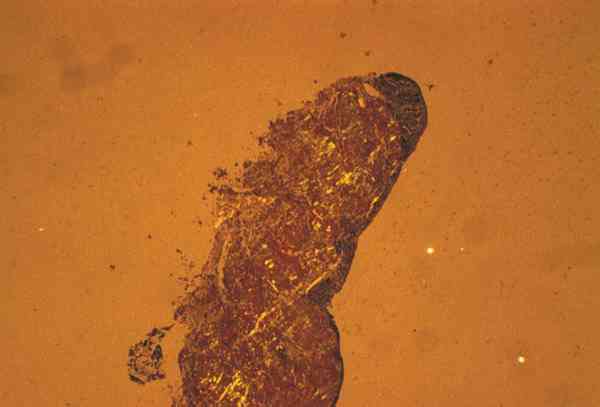

Figura 5

BIOPSIA DE LA LESIÓN. TINCIÓN CON ROJO Y CONGO Y MICROSCOPIA DE LUZ POLARIZADA.